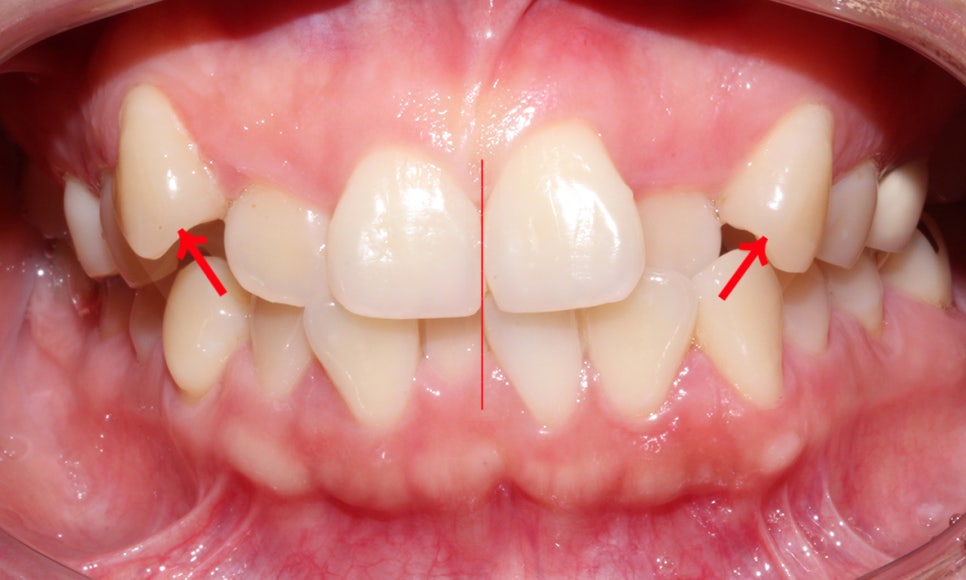

위의 사진은 상악 송곳니가

덧니로 자라난 Case로 덧니의

치아 높이를 보시면 주변 치열과 달리

확연하게 높은 위치로 벗어나 맹출된 것을

확인할 수 있습니다.

이로 인해 상악과 하악의 치아 정중선도

삐뚤어져 보이는 모습인데요,